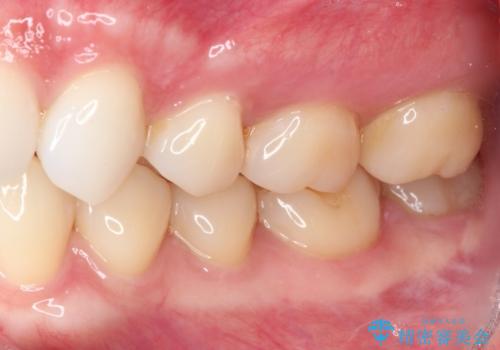

冷たいものがしみる症状はなくなり、舌で触ったときのザラザラ感もなくなりました。